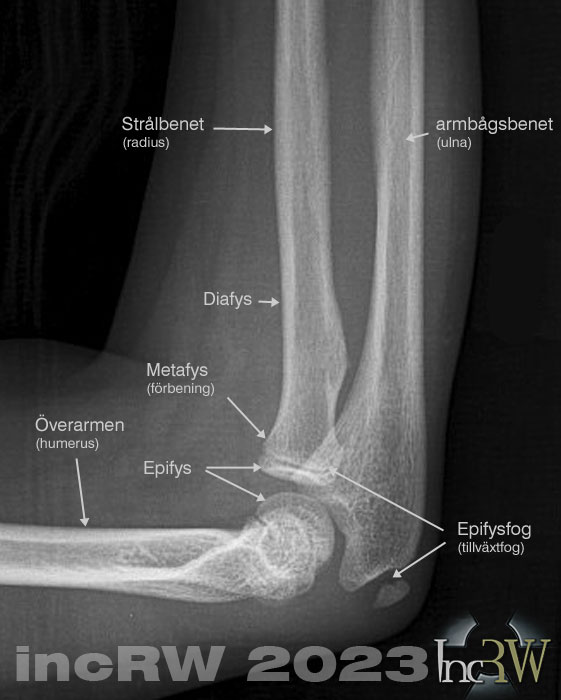

En armbågsskada hos barn som växer måste kartläggas noggrant. I stort alla benändar på barnskelettet har en tillväxtzon som kan lossna (disloseras) eller vars frakturbrott i epikondylen medför risk för nedsatt rörlighet i leden eller deformitet (felställning) i armbågen om en skada får läka fel. En fraktur genom epifysfogen kan påverka tillväxten av ben i armbågen då små blodkärl härigenom kan ta skada.

Komplexa armbågsfrakturer med benfragment som involverar ledytor eller misstänkt avlösning av epifysen kan även ibland behöva undersökas med datortomografi (CT).